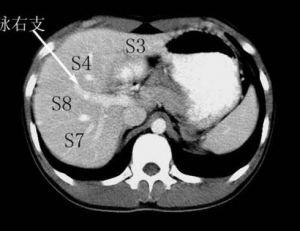

ct肝脏分段解析

肝脏ct分段

肝脏分叶分段ct图像

肝脏ct分叶分段解剖图

肝脏ct分段解剖图

肝脏分段ct断面解剖图

肝叶分段ct示意图

ct肝脏分段图

肝脏分段ct

肝脏分段8段CT